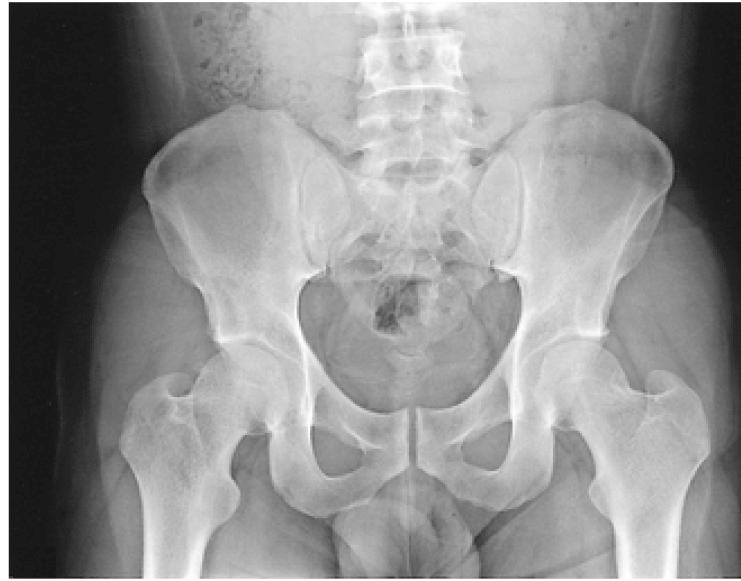

A 40-year-old Korean man presented with painful swelling and tenderness of both ankle joints as well as the plantar surfaces of both feet, along with inflammatory back pain, and a purulent discharge from the urethral orifice. The patient also complained of sicca-like symptoms including dry eyes and dry mouth. An immunological analysis revealed a high titer of rheumatoid factor, positive results for antinuclear antibody and anti-Ro antibody, and a positive result for HLA-B27. An antibody titer for Chlamydia was also significantly increased. Positive results of the Schirmer's test and for keratoconjunctivitis sicca were confirmed by an ophthalmologist. These clinical manifestations were compatible with Chlamydia-induced reactive arthritis (ReA) accompanied by Sjögren's syndrome (SS). This is the first report of the combination of these two distinct disease entities in the Korean population.

一名40岁的韩国男性出现双踝关节以及双足底疼痛性肿胀和压痛,伴有炎性背痛,尿道口有脓性分泌物。患者还主诉有干眼症和口干等类似干燥综合征的症状。免疫分析显示类风湿因子滴度高、抗核抗体和抗Ro抗体结果呈阳性以及HLA - B27结果呈阳性。衣原体抗体滴度也显著升高。眼科医生证实了泪液分泌试验和干燥性角结膜炎结果呈阳性。这些临床表现符合衣原体诱导的反应性关节炎(ReA)伴干燥综合征(SS)。这是韩国人群中这两种不同疾病实体合并出现的首例报告。